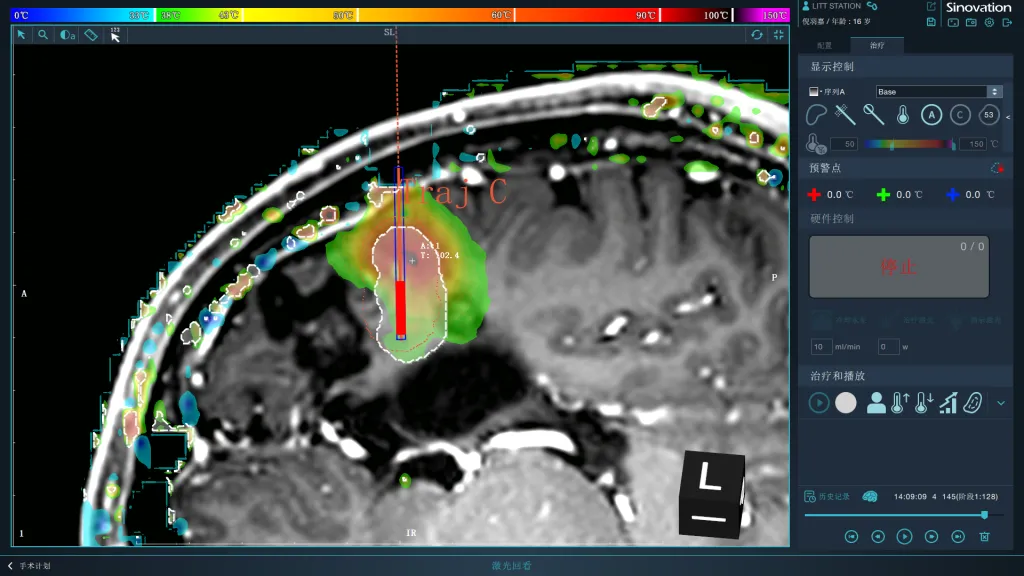

在磁共振室,团队置入激光散射光纤并连接消融设备及冷却水路,通过核磁共振定位像实时传输影像至激光消融仪,以8-10瓦功率对左额4处致痫灶靶点进行精准消融。

激光消融过程